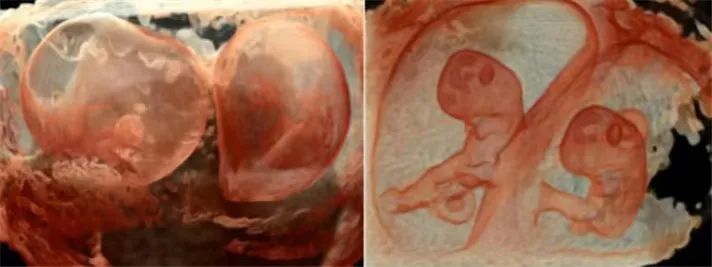

“煊影成像”技术可以清晰显示胎儿的内部结构,增加组织透明度调节,实现100级可调,从内到外,一览无余。在早孕、双胎等评估方面极具优势。

“煊流技术”可真实呈现脐带、胎盘血流,对于深部小血管的立体结构显示极具优势,在评估血管分布或灌注状态时,如同采用血管造影模式。提升产前检查的诊断质量和效率。